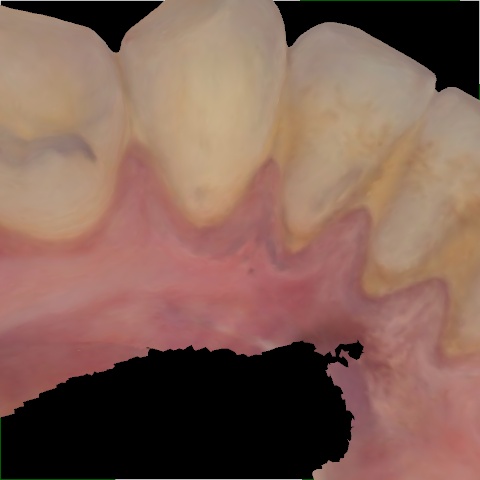

Annotated as "Good"